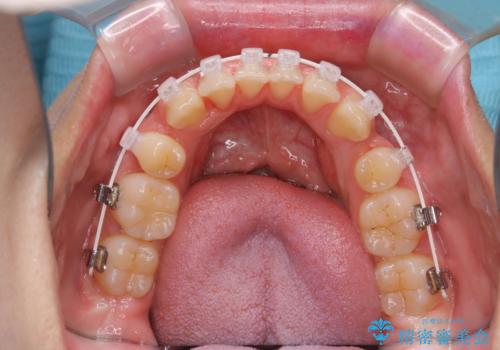

ワイヤー矯正中のクリーニング

- ワイヤー矯正中に、磨ききれないところがあるのと、口臭が気になるとのことでした。

そのためPMTC30分コースを行いました。

ワイヤー矯正中は、装置の周りに汚れが付きやすく虫歯や歯周病のリスクが高まります。そのため、ワイヤー調整の診察の際、一緒にクリーニングを行うことで、虫歯・歯周病・口臭予防になります。歯ブラシだけでは取り除くことが難しい細かい部分などに、専門的な機械や機材を使用して定期的なケアを行うことをおすすめしています。